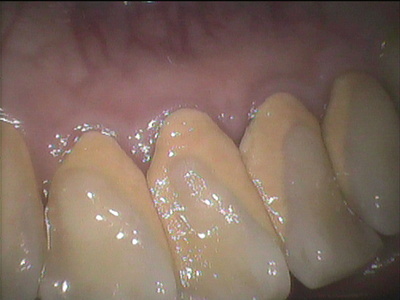

お口の中にいるばい菌が原因で歯の周辺の組織をダメにしていく病気です。

人間の口の中には数百種類の細菌がいます。

その中には口の中の環境を保つのに必要な細菌もたくさん含まれています。

長期的には菌交代現象が起こり、殺菌剤で死なないばい菌だらけになる恐れもあります。の400種類の細菌の中で、歯周病の原因にはこの6つが代表的なものです。